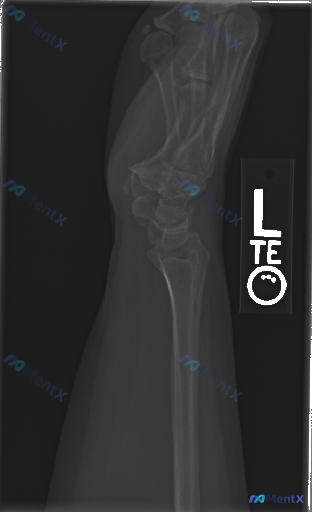

这张左腕关节侧位X线片的“不规则感”,你会先考虑什么?

- 投照:左腕关节侧位(标记「L」),投照质量尚可,腕骨重叠符合侧位片基本特征

- 骨皮质与骨折:桡骨远端关节面骨皮质连续性完整,未见明确骨折线、台阶感或成角;舟骨、月骨、头状骨、三角骨等主要腕骨未见明显骨皮质中断或错位;头月关联位置骨质连续,无明确脱位征象;可见部分掌骨基底,无骨折迹象

- 关节对位:桡骨远端、月骨、头状骨纵轴排列大致呈直线,无明显阶梯状错位;无月骨掌侧翻转,无头骨相对于月骨的移位

- 骨质密度与退变:骨小梁清晰,皮质光整,无明显骨质疏松或异常密度改变;关节面边缘光滑,无明显骨赘、硬化或囊性变,无游离体

- 软组织:掌侧与背侧软组织轮廓尚平滑,无明显肿胀或异常增厚;无明显异物影或肌腱钙化灶

本次左腕关节侧位X线片显示左腕部骨结构完整,各骨间关节对位关系良好,未见明显的骨折、脱位或骨质破坏征象,软组织未见明显肿胀。